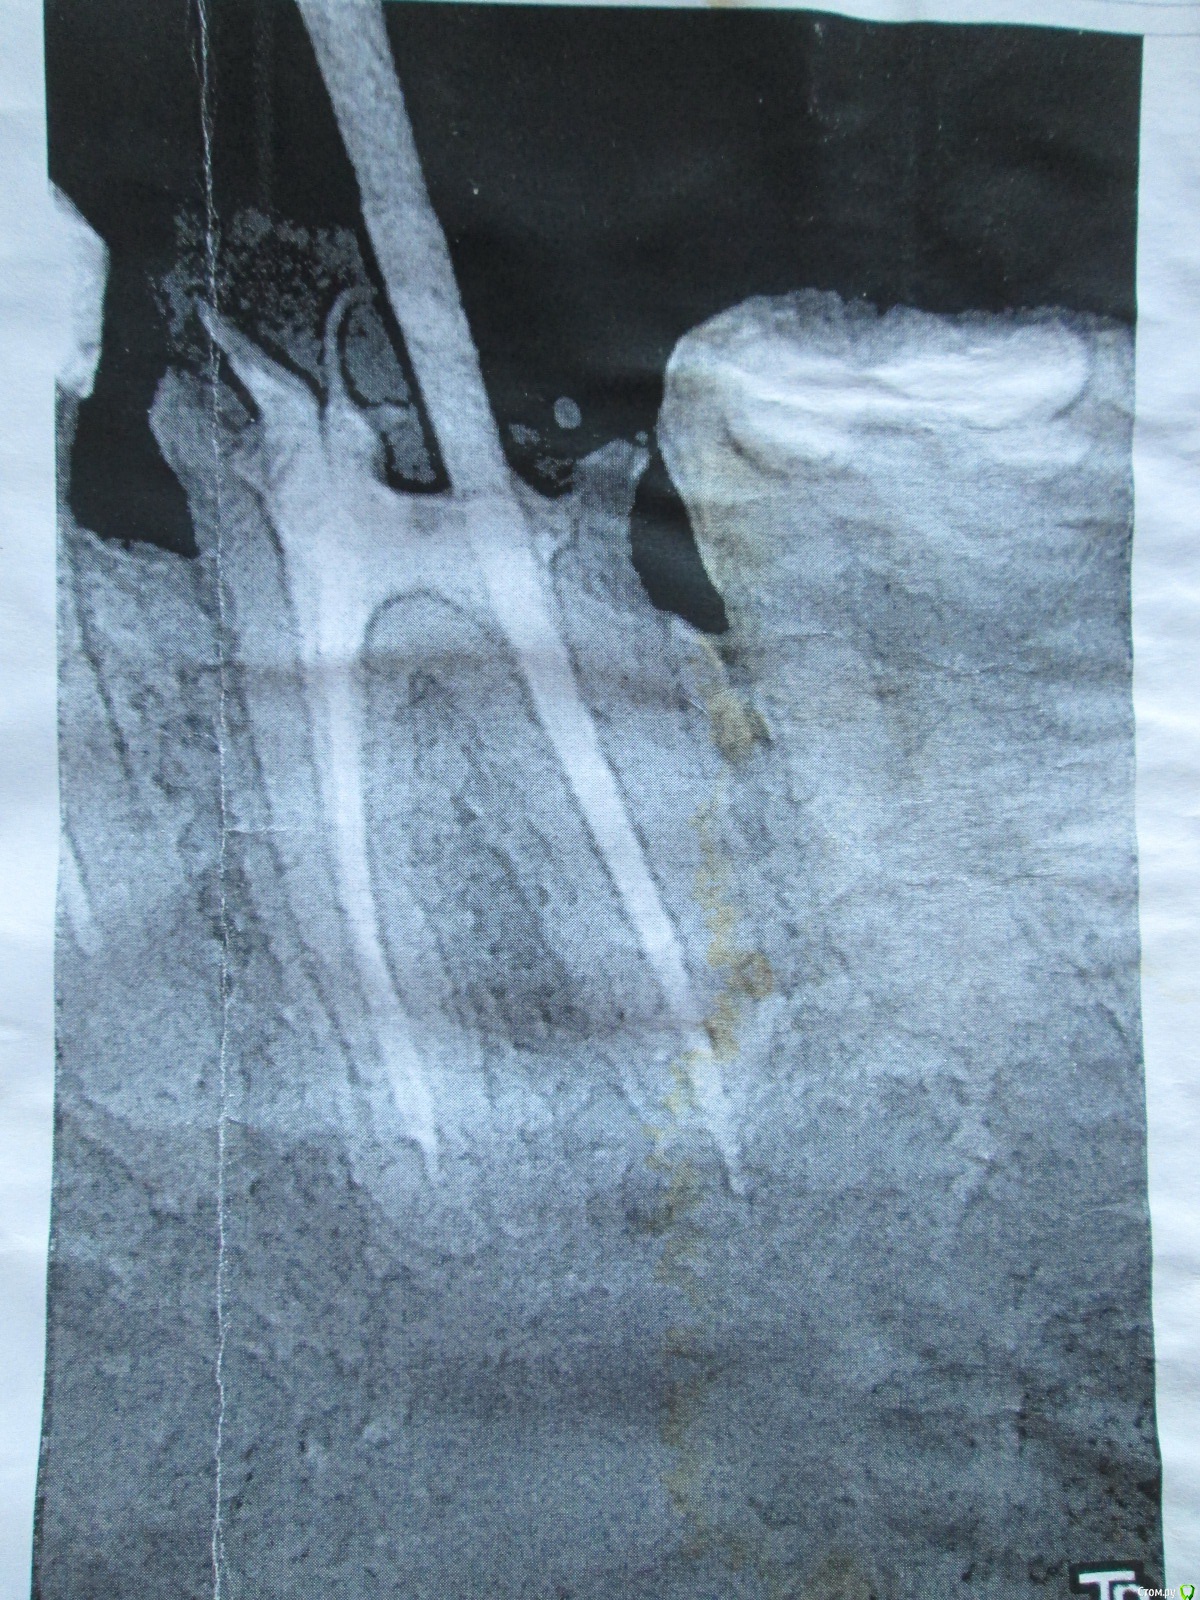

LOLga777 Опубликовано 24 ноября, 2019 Поделиться Опубликовано 24 ноября, 2019 (изменено) Здравствуйте, уважаемые врачи.37-й зуб. Депульпирован, стояла большая пломба. В 2013 году откололась наружная стенка зуба, скол близко к корню. Стоматологом № 1 был поставлен штифт, коронка восстановлена пломбой (фото с торчащим штифтом от 2013 года). Через год наружная часть пломбы откололась прямо по штифту, так ходила три года, ничего не царапало, не мешало. В 2016 году стоматолог № 2 в поликлинике уговорила запломбировать, в результате сделала скошенную наружную часть пломбы. Фото ротовой полости справа от 07.2019 г. прилагаю. Вопрос: что делать с 37-й зубом? Хирург не хочет удалять, говорит, что можно восстановить пломбой, и боится повредить 36-й. Не знаю, видно ли на снимках, в каком канале стоит штифт и можно ли поставить еще один штифт (второй штифт врач не поставила, насколько я помню, из-за того, что будет дороже и еще что-то там может не выдержать). Без второго штифта пломба, повторяющая анатомическую форму зуба, я считаю, простоит максимум год. С 36-м зубом тоже непонятно что делать, не идет ли там процесс кариеса на корне… Между корнями что-то черное (на КТ и 2016 года и 05.2019 года). Не хотелось бы покрывать коронкой зуб с гранулемой между корнями. Стоматолог предложил рассверлить пломбу и посмотреть.У меня ВОПРОС: можно ли будет что-то увидеть после рассверливания зуба, если процесс идет под «дном»? После сверления снимется еще часть тканей, а их там и так мало. По вкладкам и коронкам на 37-й зуб, наверное, надо продублировать тему в раздел «Протезирование». P.s. Есть большое количество других проблем Изменено 24 ноября, 2019 пользователем LOLga777 Ссылка на комментарий

LOLga777 Опубликовано 25 ноября, 2019 Автор Поделиться Опубликовано 25 ноября, 2019 Тогда и к ортодонту не грех за направлением и консультацией забежатьЗаходила... бумагу надо было взять...И меня все-таки интересует, что можно увидеть между корней после рассверливания № 37. Мне кажется, что ничего, на то он и межкорневой процесс. Мне не очень понятно желание отдельных врачей пломбировать этот зуб... Ссылка на комментарий